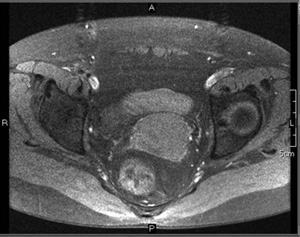

骨盤領域は脂肪組織に富むため,脂肪抑制が難しい部位の1つである。子宮病変検査へのH-sincパルスの適用例を図1に示す。本図から,安定して脂肪が抑制されていることがわかる。

図1 骨盤部画像例

a:H-sinc併用T1WI

b:T2WIc:H-sin

c:H-sinc併用DWI(b=50s/mm2)

d:H-sinc併用(b=800s/mm2)